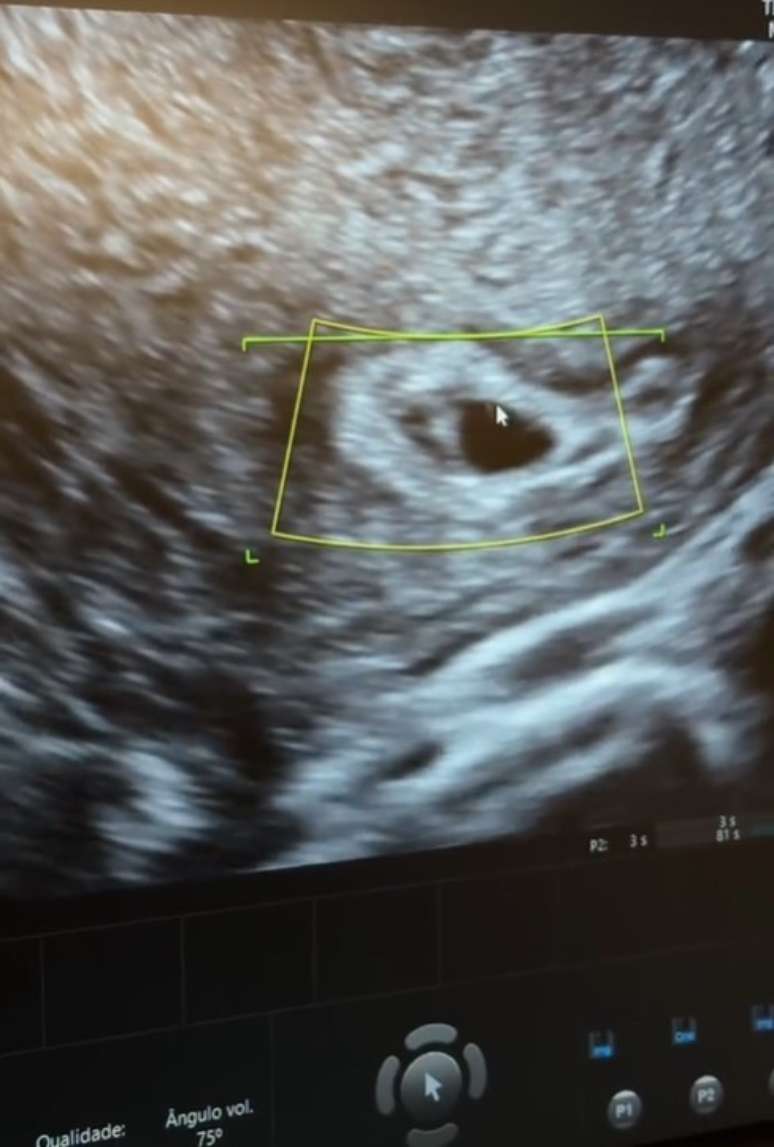

Na tarde da última quarta-feira (11), Maíra Cardi foi ao ginecologista ao lado do marido, Thiago Nigro. A influenciadora fez seu primeiro ultrassom do terceiro filho, primeiro com o atual marido. E em seu perfil no Tik Tok, a ex-BBB publicou vídeo e pulou de alegria.

Após o exame, a influenciadora celebrou muito ao saber as boas notícias do filho: "Só boas notícias, o bebê está bem implantado. Tudo normal, estamos muito felizes. O bebê está com 5 semanas e 1 um dia de vida", disse ela, muito emocionada. De acordo com o obstetra que acompanha a gestação da artista, a previsão para dar à luz ao pequeno é no mês de agosto de 2025. Nesse período, Maíra estará com 40 semanas.